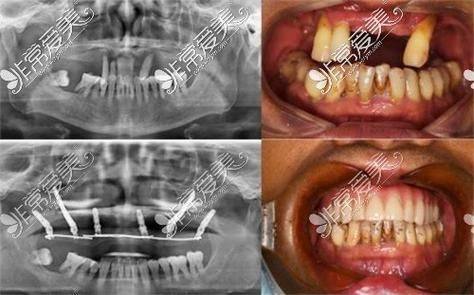

牙齿缺失修复:精通牙列缺失种植修复、种植牙治疗,可适配多种种植体类型,帮助患者修复正常咀嚼功能与口腔美观度。

咬合重建综合治疗:能够开展复杂的咬合重建综合诊疗,解决咬合紊乱引发的各类口腔不适,提升患者整体口腔健康水平。